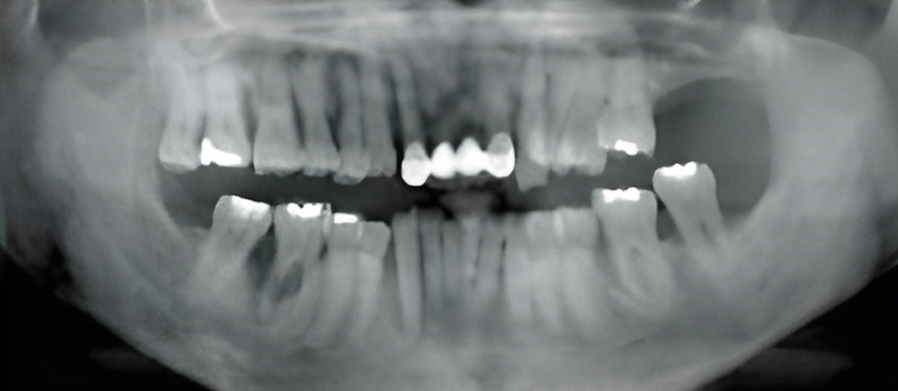

When a tooth is severely damaged or decayed, an infection can form and spread to the nerve tissue and pulp. To repair and save the tooth, a root canal treatment is performed by our endodontist. During the root canal procedure, the infected nerve and pulp are removed and the inside of the tooth is cleaned and sealed.

Some symptoms that can indicate the need for a root canal are persistent pain while chewing or biting, sensitivity to hot or cold, swollen or tender gums, tooth discoloration, chipped or cracked teeth, and pimples on the gums.

A tooth that has had a root canal treatment is not as sturdy as before, due to the removal of a large portion of the pulp. Thus it is common that the root canal treatment is followed by restorative procedures to place a post, core and crown.

With over 20 years of experience, Dr. Hyo-Jin Lee prioritizes patient comfort and tries to make the procedure as pain-free as possible. Root canal treatment usually takes about one to three visits depending on the condition of the tooth.

The primary cause of periodontal disease is the accumulation of bacterial plaque at and under the gum line.

If plaque is not removed daily through brushing and flossing, the bacteria will cause the gum tissue to become red and swollen. At this first stage, gingivitis can and may be reversed by visiting your dentist and dental hygienist, along with your efforts at maintaining good dental hygiene.

If gingivitis is left untreated, the plaque can spread to the roots, causing an infection and damage to the supporting bone and soft tissue. The gums may separate from the tooth and start to recede. A pocket can form below the gum line and trap plaque and food. As periodontitis progresses, up to one-third of the bone can be lost.

In this later stage, half or more of the original bone holding the tooth is lost, and the pocket becomes very deep. The gums recede even more and the tooth may appear longer because the root is exposed. The tooth may eventually fall out due to a lack of supporting bone.